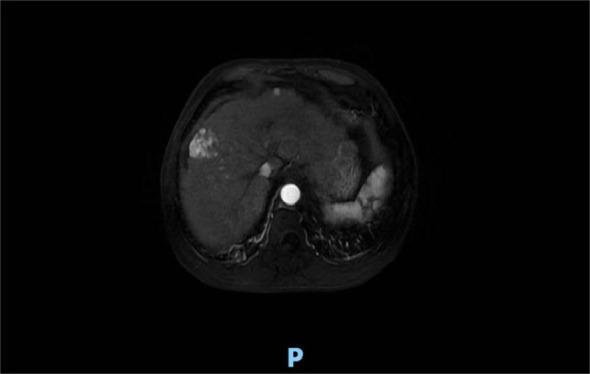

臀中肌转移的肝细胞癌治疗:1例病例报告及文献复习

Treatment of hepatocellular carcinoma with gluteus medius metastasis: a case report and a literature review.

Hepatocellular carcinoma (HCC) accounts for 85%-90% of all primary liver cancers (PLCs). Owing to the occult nature of HCC, most patients present at an advanced stage at the time of initial diagnosis and have a poor prognosis. With regard to systemic therapy, targeted therapy and immunotherapy are currently the centers of clinical research. With regard to local treatment, surgical resection, radiofrequency ablation, hepatic artery chemoembolization, and radiotherapy are commonly used. Interstitial brachytherapy is commonly used for the treatment of cervical and genitourinary cancers. In this case, interstitial brachytherapy was used to treat gluteus medius muscle metastasis from PLC, with good local control and symptom relief.

摘要

肝细胞癌(HCC)占所有原发性肝癌(PLC)的85%-90%。由于HCC具有隐匿性,大多数患者在初诊时已处于晚期,预后较差。在全身治疗方面,靶向治疗和免疫治疗是目前临床研究的重点。在局部治疗方面,手术切除、射频消融、肝动脉化疗栓塞和放射治疗是常用的方法。间质近距离放射治疗常用于治疗宫颈癌和泌尿生殖系统癌症。在本病例中,间质近距离放射治疗被用于治疗PLC的臀中肌转移,局部控制良好,症状得到缓解。